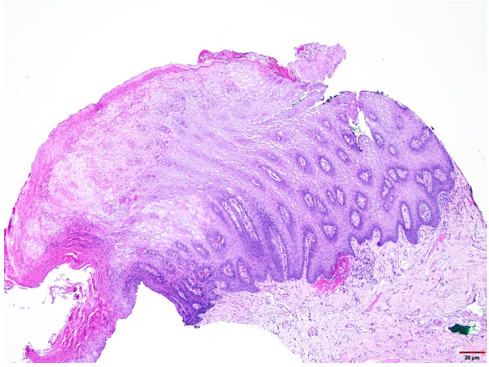

The formalin-fixed tissue specimen was subjected to routine processing after which 5μm sections were cut and stained with hematoxylin and eosin. The tissue sections showed hyperkeratinized surface mucosal epithelium supported by lamina propria (Figure 4). The epithelium was covered by a thick layer of parakeratin. The spinous cell layer was thickened and showed superficial layers of cells exhibiting prominent deeply chromatic nuclei surrounded by vacuolated cytoplasm imparting optically clear cells (Figure 5). The basal and suprabasal layers of cells exhibited the normal cellular maturation pattern without any cellular or nuclear atypia (Figure 6). Subepithelial inflammatory cell infiltrates were noted in the superficial lamina propria. A diagnosis of “Hyperparakeratosis with prominent perinuclear vacuolization of the epithelium”, consistent with Pachyonychia congenita was made.

Figure 4: Tissue section exhibiting hyperkeratinized surface mucosal epithelium supported by lamina propria